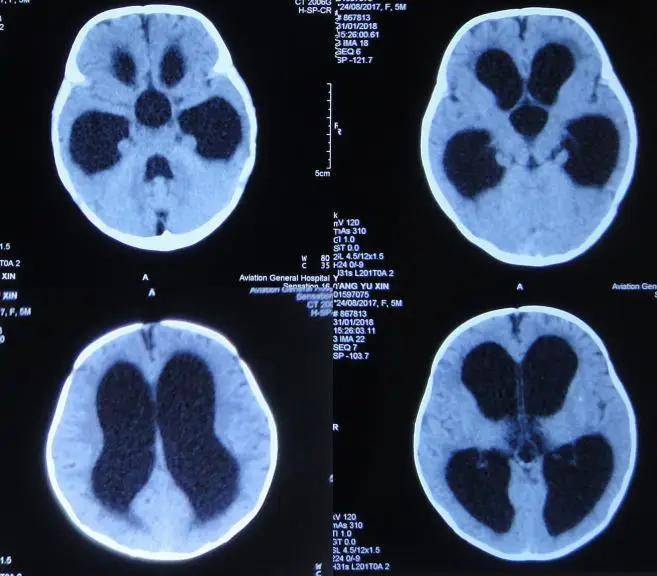

脑积水的症状主要包括以下几点颅内压增高症状头痛通常为持续性或阵发性加剧的头痛,多位于前额或双颞侧呕吐常发生在清晨,多为喷射性呕吐,与颅内压增高刺激呕吐中枢有关视力障碍表现为视力减退复视或外展神经麻痹等,与颅内压增高导致视神经乳头水肿有关智能障碍表现为记忆力减退。

恶心呕吐,可以看到视乳头水肿同时,对于一些长期慢性颅内压增高患者,可以表现为有行走困难共济失调的症状,一种宽基底步态还有一部分患者可以表现出来进行性进展的认知功能障碍,出现记忆力下降计算能力下降言语功能障碍行为功能障碍等称为痴呆,跟脑积水压迫有关系,还会出现小便失禁的症状。